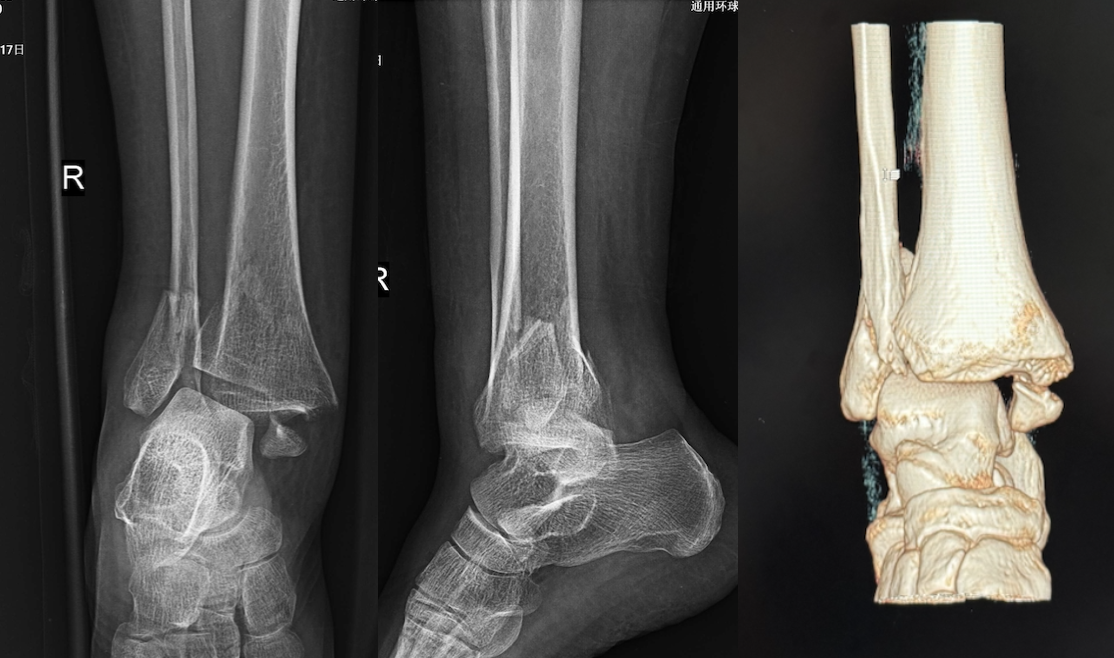

10月1日晚,惠女士被家属紧急送至我院急诊科,当时右踝部严重畸形、肿胀,伴剧烈疼痛,局部出现张力性水泡,被诊断为三踝骨折,情况紧急。患者和家人担心长假难以得到及时有效的治疗。

术前